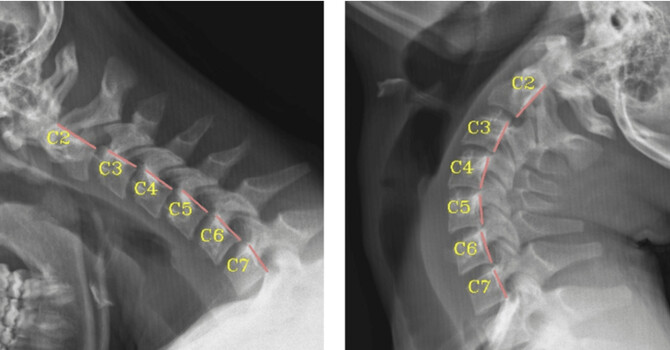

• Altered sagittal alignment (side-view curvature changes)

Evaluation of scoliosis involves a structured clinical assessment focused on spinal alignment, posture, and biomechanical function. A scoliosis evaluation may include:

• Postural and spinal alignment assessment

• Review of imaging studies when clinically indicated